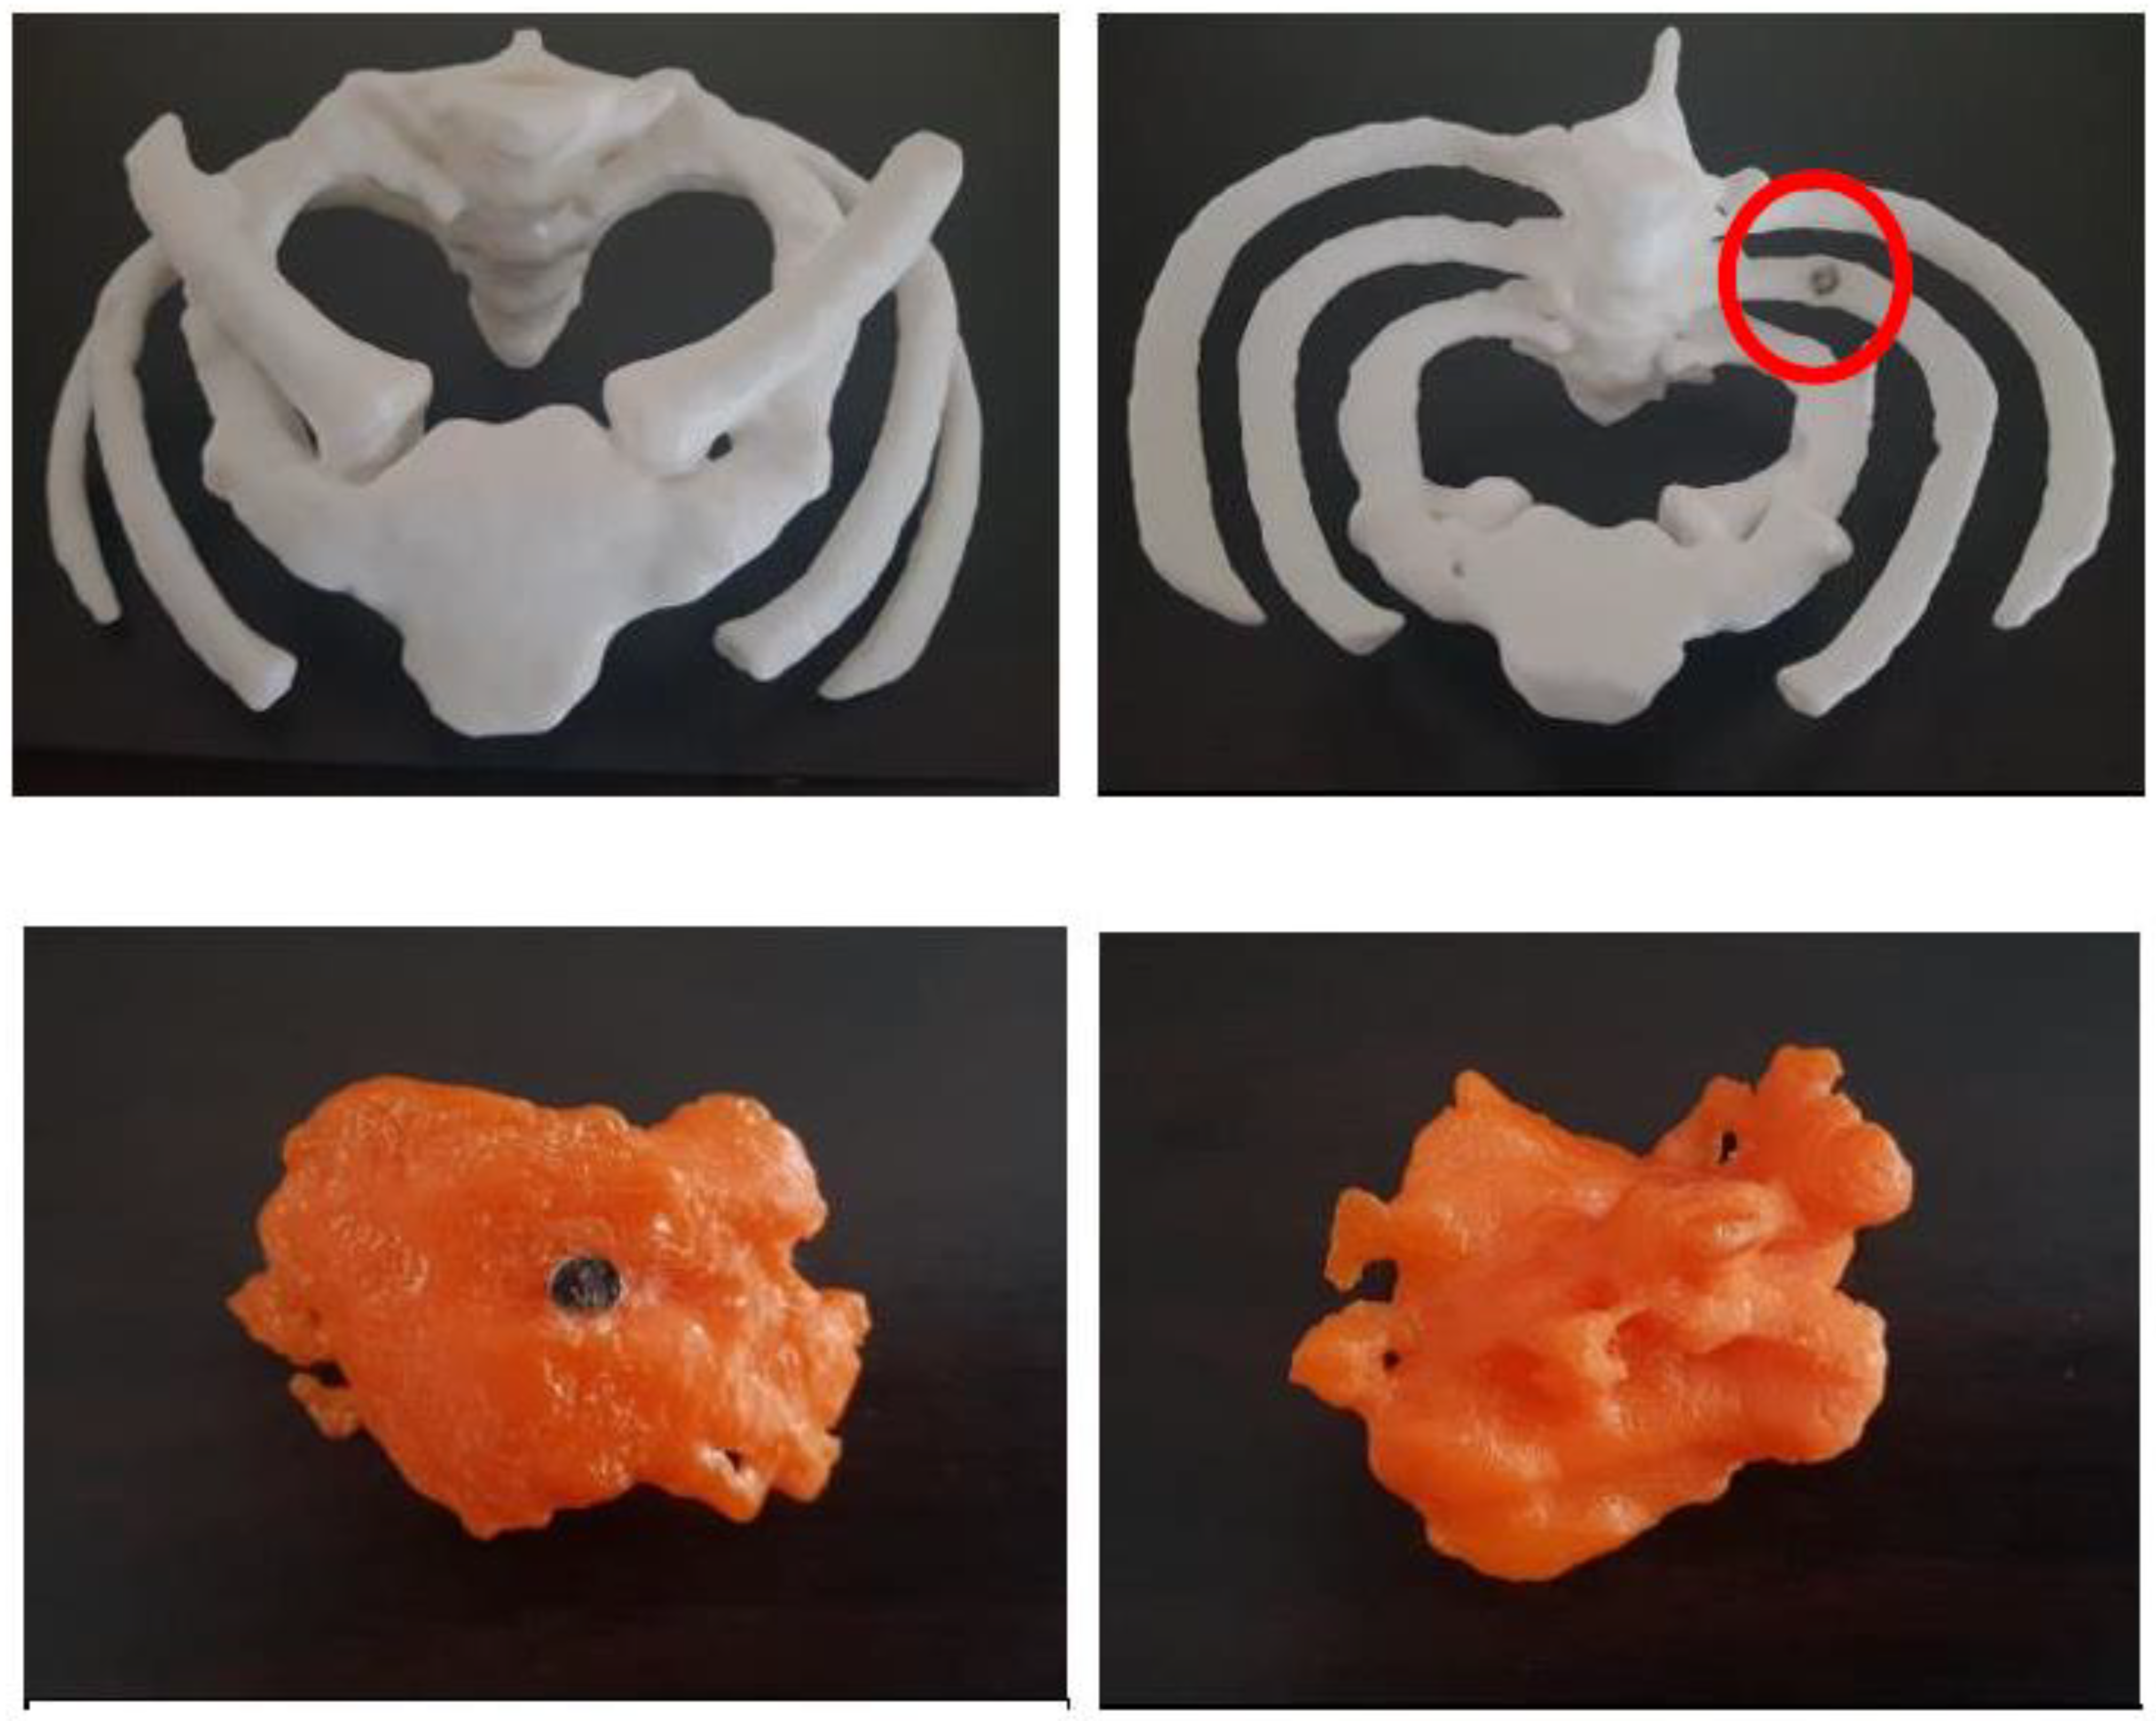

5.7. 3D-Printed Models of Abdominal and Pelvic Organs

| Abdomen and pelvis | Stomach: 1 Kidneys: 1 Spleen: 1 Bladder: 1 Uterus: 1 Skeleton: 1 | CT | Multiple organs for a case of situs ambiguus | Printer: Skeleton was printed using Raise3D N2 Plus (Raise3D, USA) Other organs were printed using Ultimaker 2+ Extended (Ultimaker BV, Netherland) Material: Skeleton: PLA Other organs: TPU 95A Cost: USD 55 for skeleton and USD 75 for other organs | Skeleton was printed with a resolution of 12.5 μm for the x and y-axis planes and 10 μm for z-axis plane Other organs were printed at a resolution of 12.5 μm for the x, y and z-axis plane Time: Skeleton: ~250 h Other organs: ~250 h |